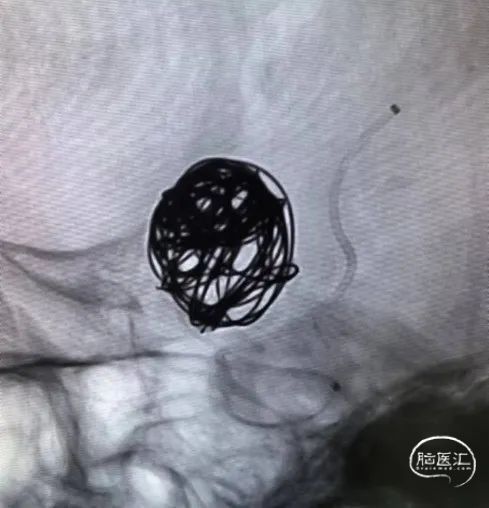

拟行血流导向密网支架置入+弹簧圈栓塞术。

3D弹簧圈 16*52、20*50

随后经支架微导管输送Nuva®血流导向密网支架 TJED-D-5.5-16到位,头端打开“V”字形后整体回撤系统至头端锚定位置,开始释放支架,过弯处推拉结合使支架更好打开,尾端减张缓慢释放。释放过程中分次造影并调整工作位,保证支架位置理想及打开良好。交换导丝简单按摩使支架在血管迂曲处更好贴壁。